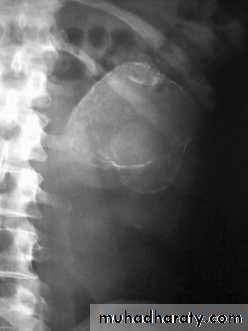

Plain x-raycalcified kidney

Multiple ureteral strictures. Strictures associatedwith dilated ureter, infundibular stenosis and caliectasis